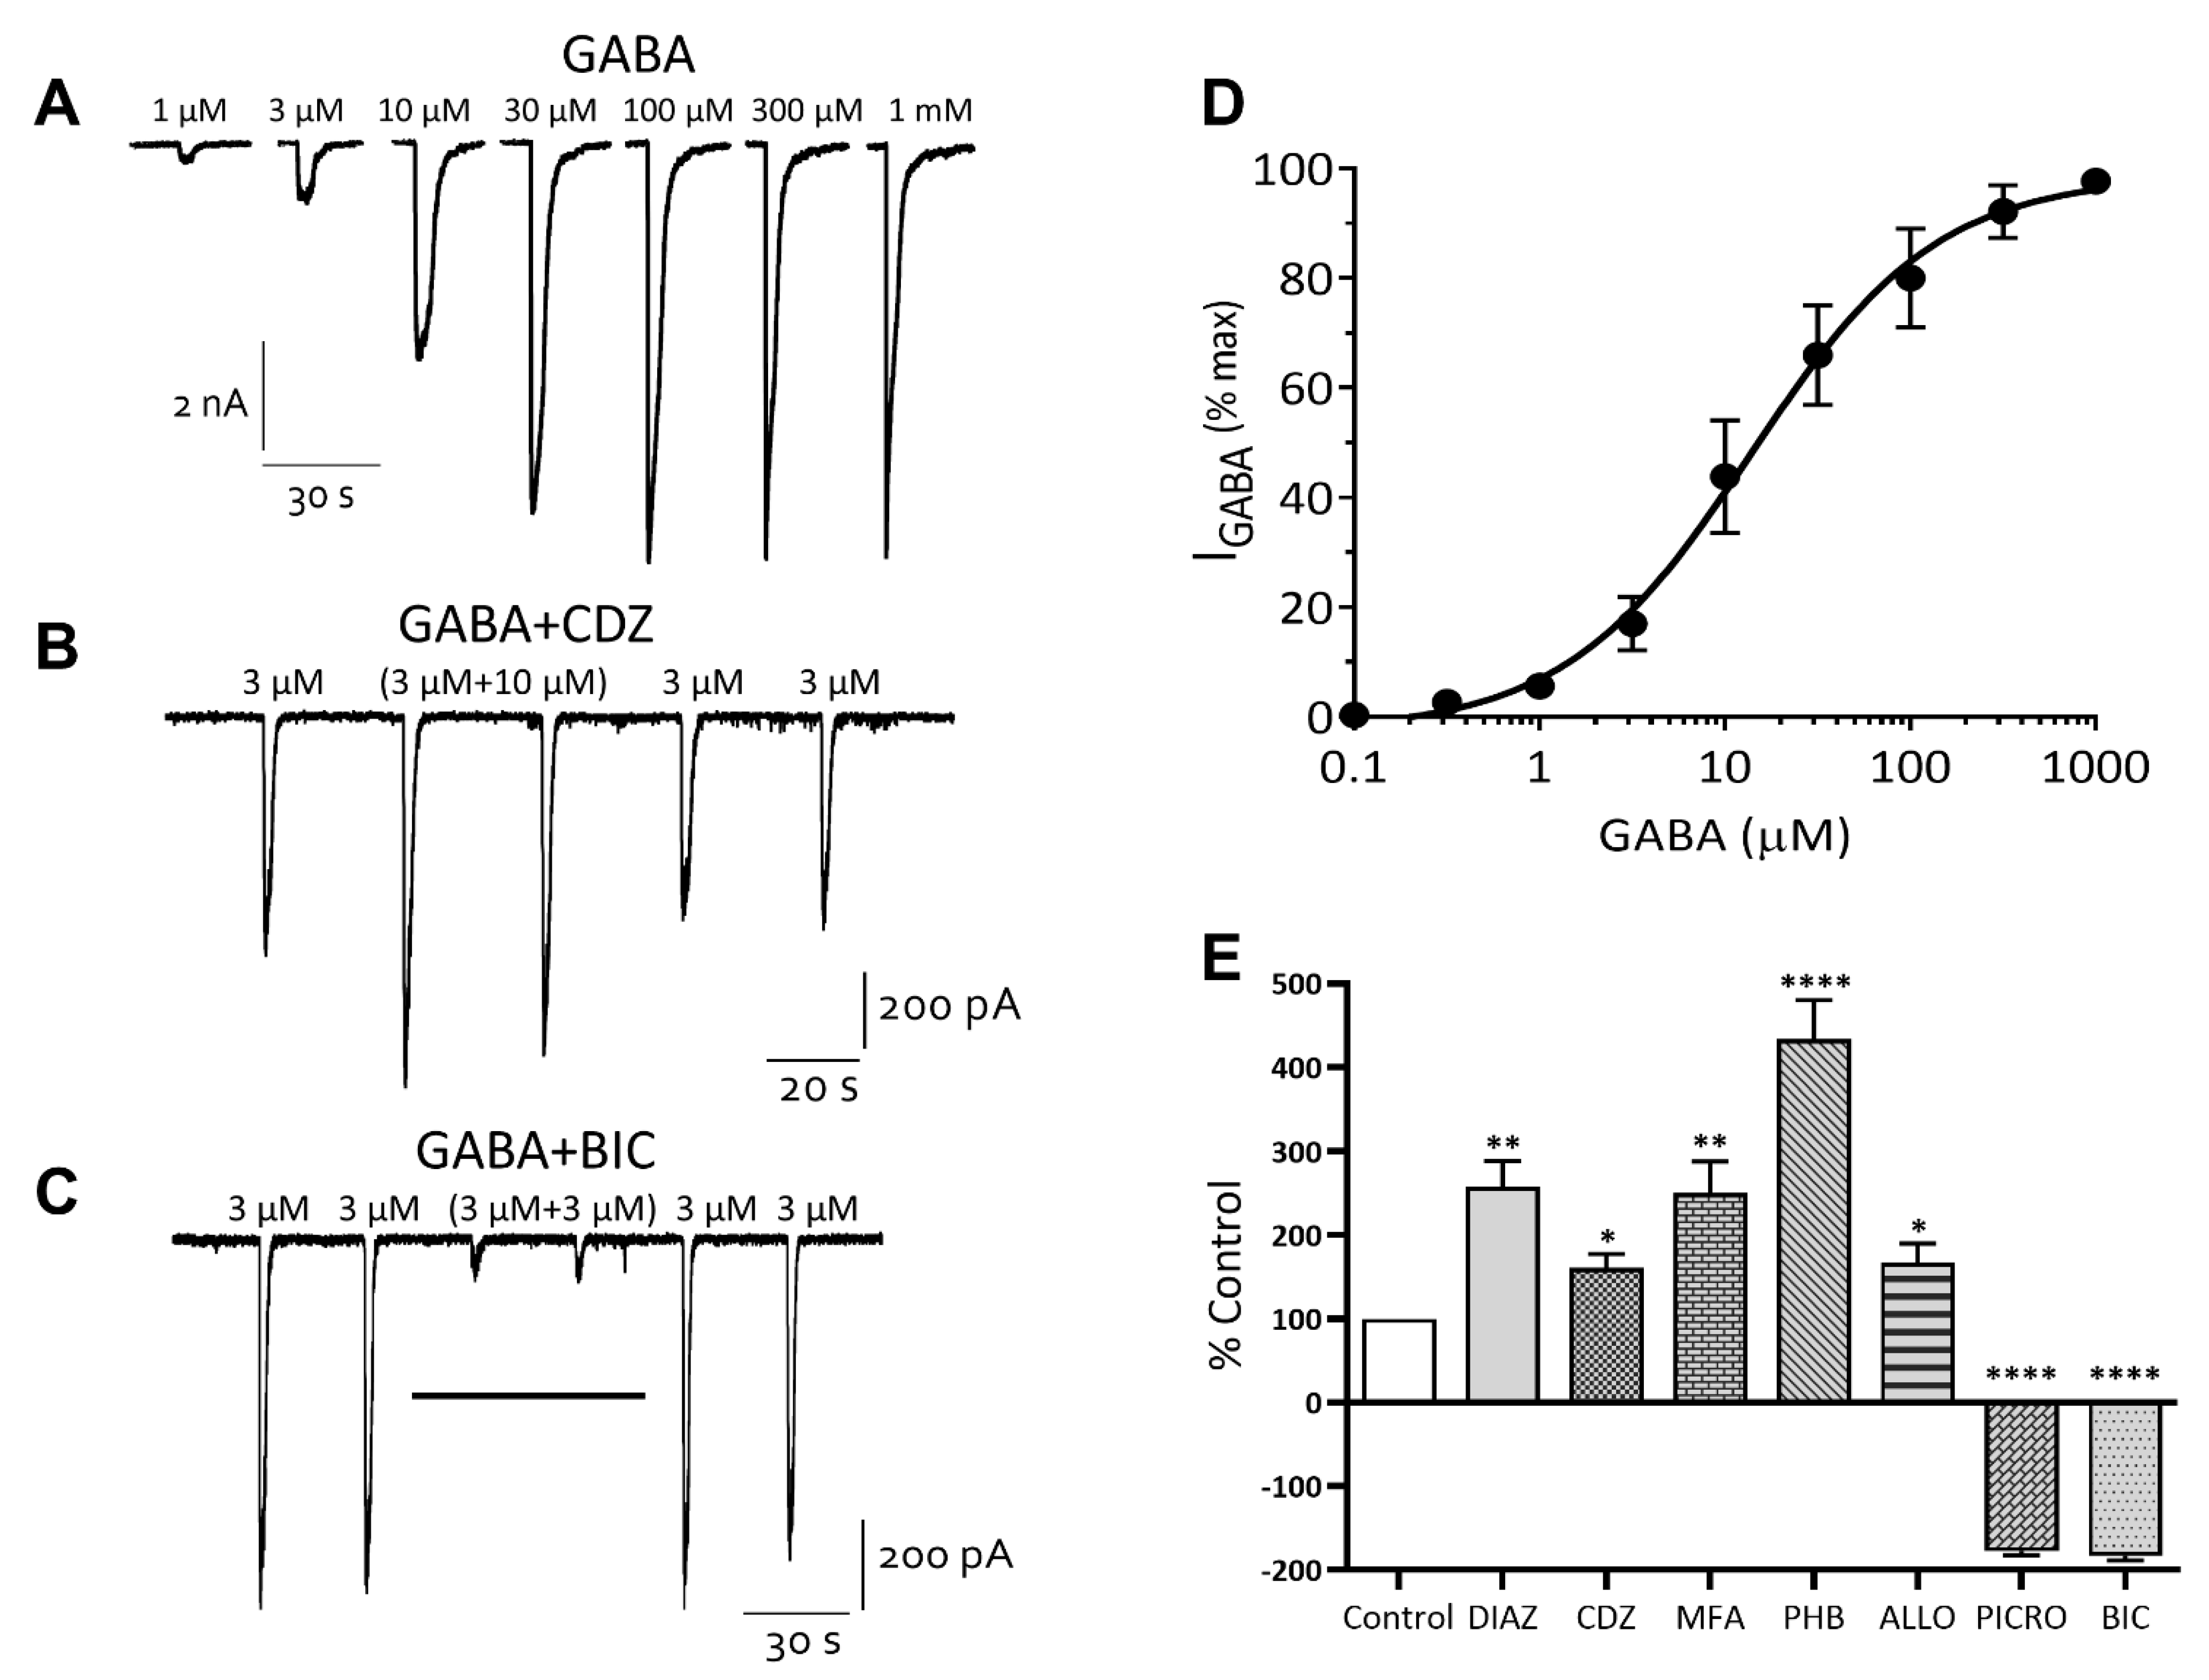

Inhibitory Ligand-Gated Currents